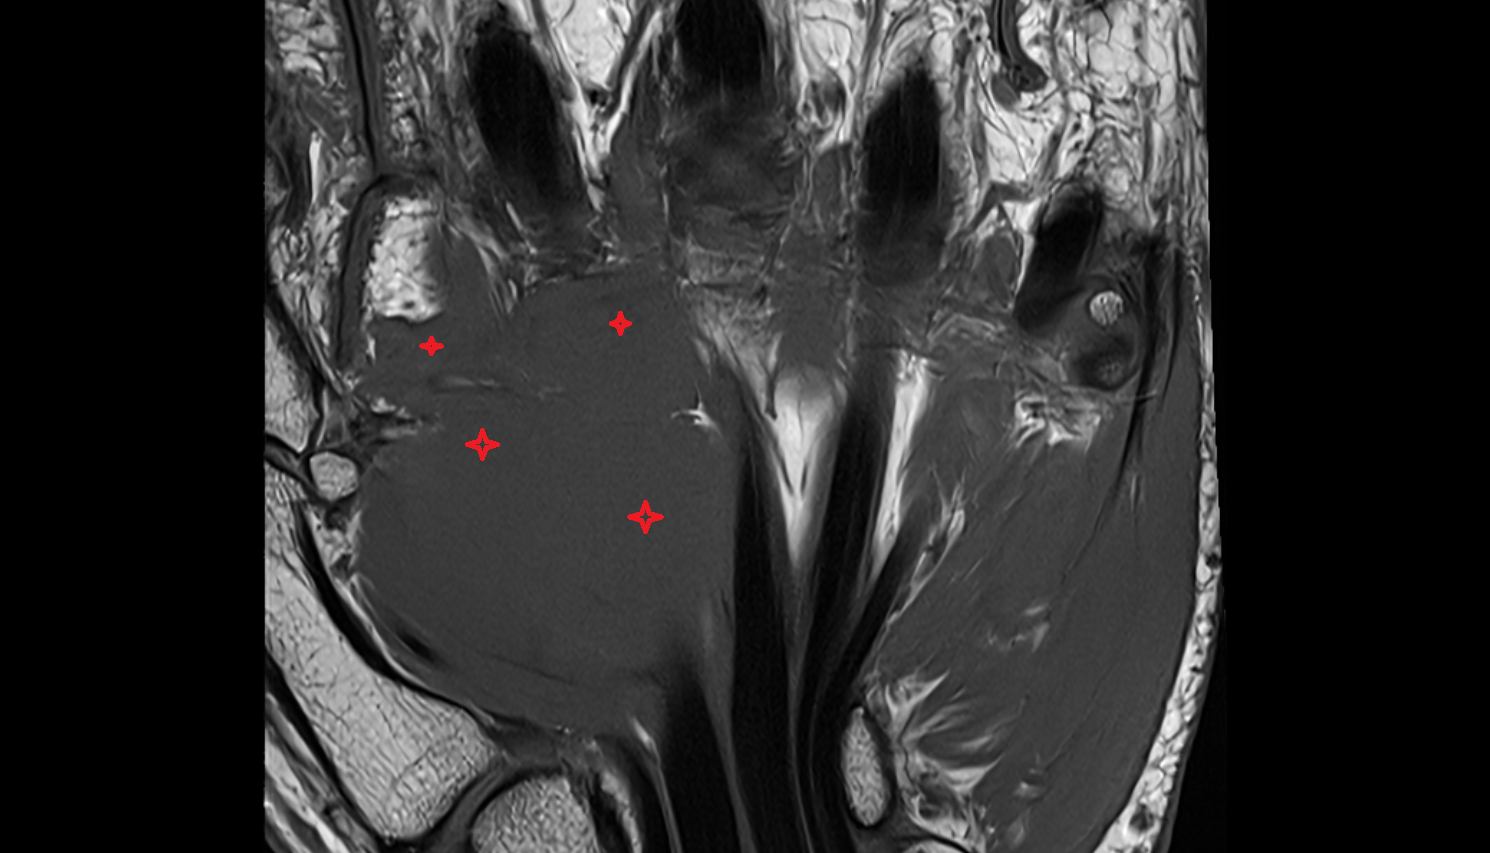

- Uterus

- Body of uterus

- Fundus of uterus

- Cervix of uterus

- Isthmus of uterus

- Vagina

- Fornix of the vagina

- Endometrium of uterus

- Myometrium of uterus

- Perimetrium of uterus

- Junctional zone of uterus